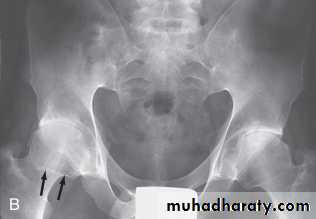

In established AS, radiographs of the sacroiliac joint show irregularity and loss of cortical margins, widening of the joint space and subsequently sclerosis, joint space narrowing and fusion.

Erosive changes may be seen in the symphysis pubis, the ischial tuberosities and peripheral joints.